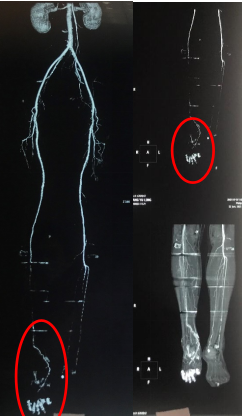

枯木逢春——我院骨科应用“胫骨横向骨搬运技术” 治疗一例严重糖尿病足并获得满意效果 关键字:骨科 糖尿病足 糖尿病足是糖尿病的严重并发症之一...